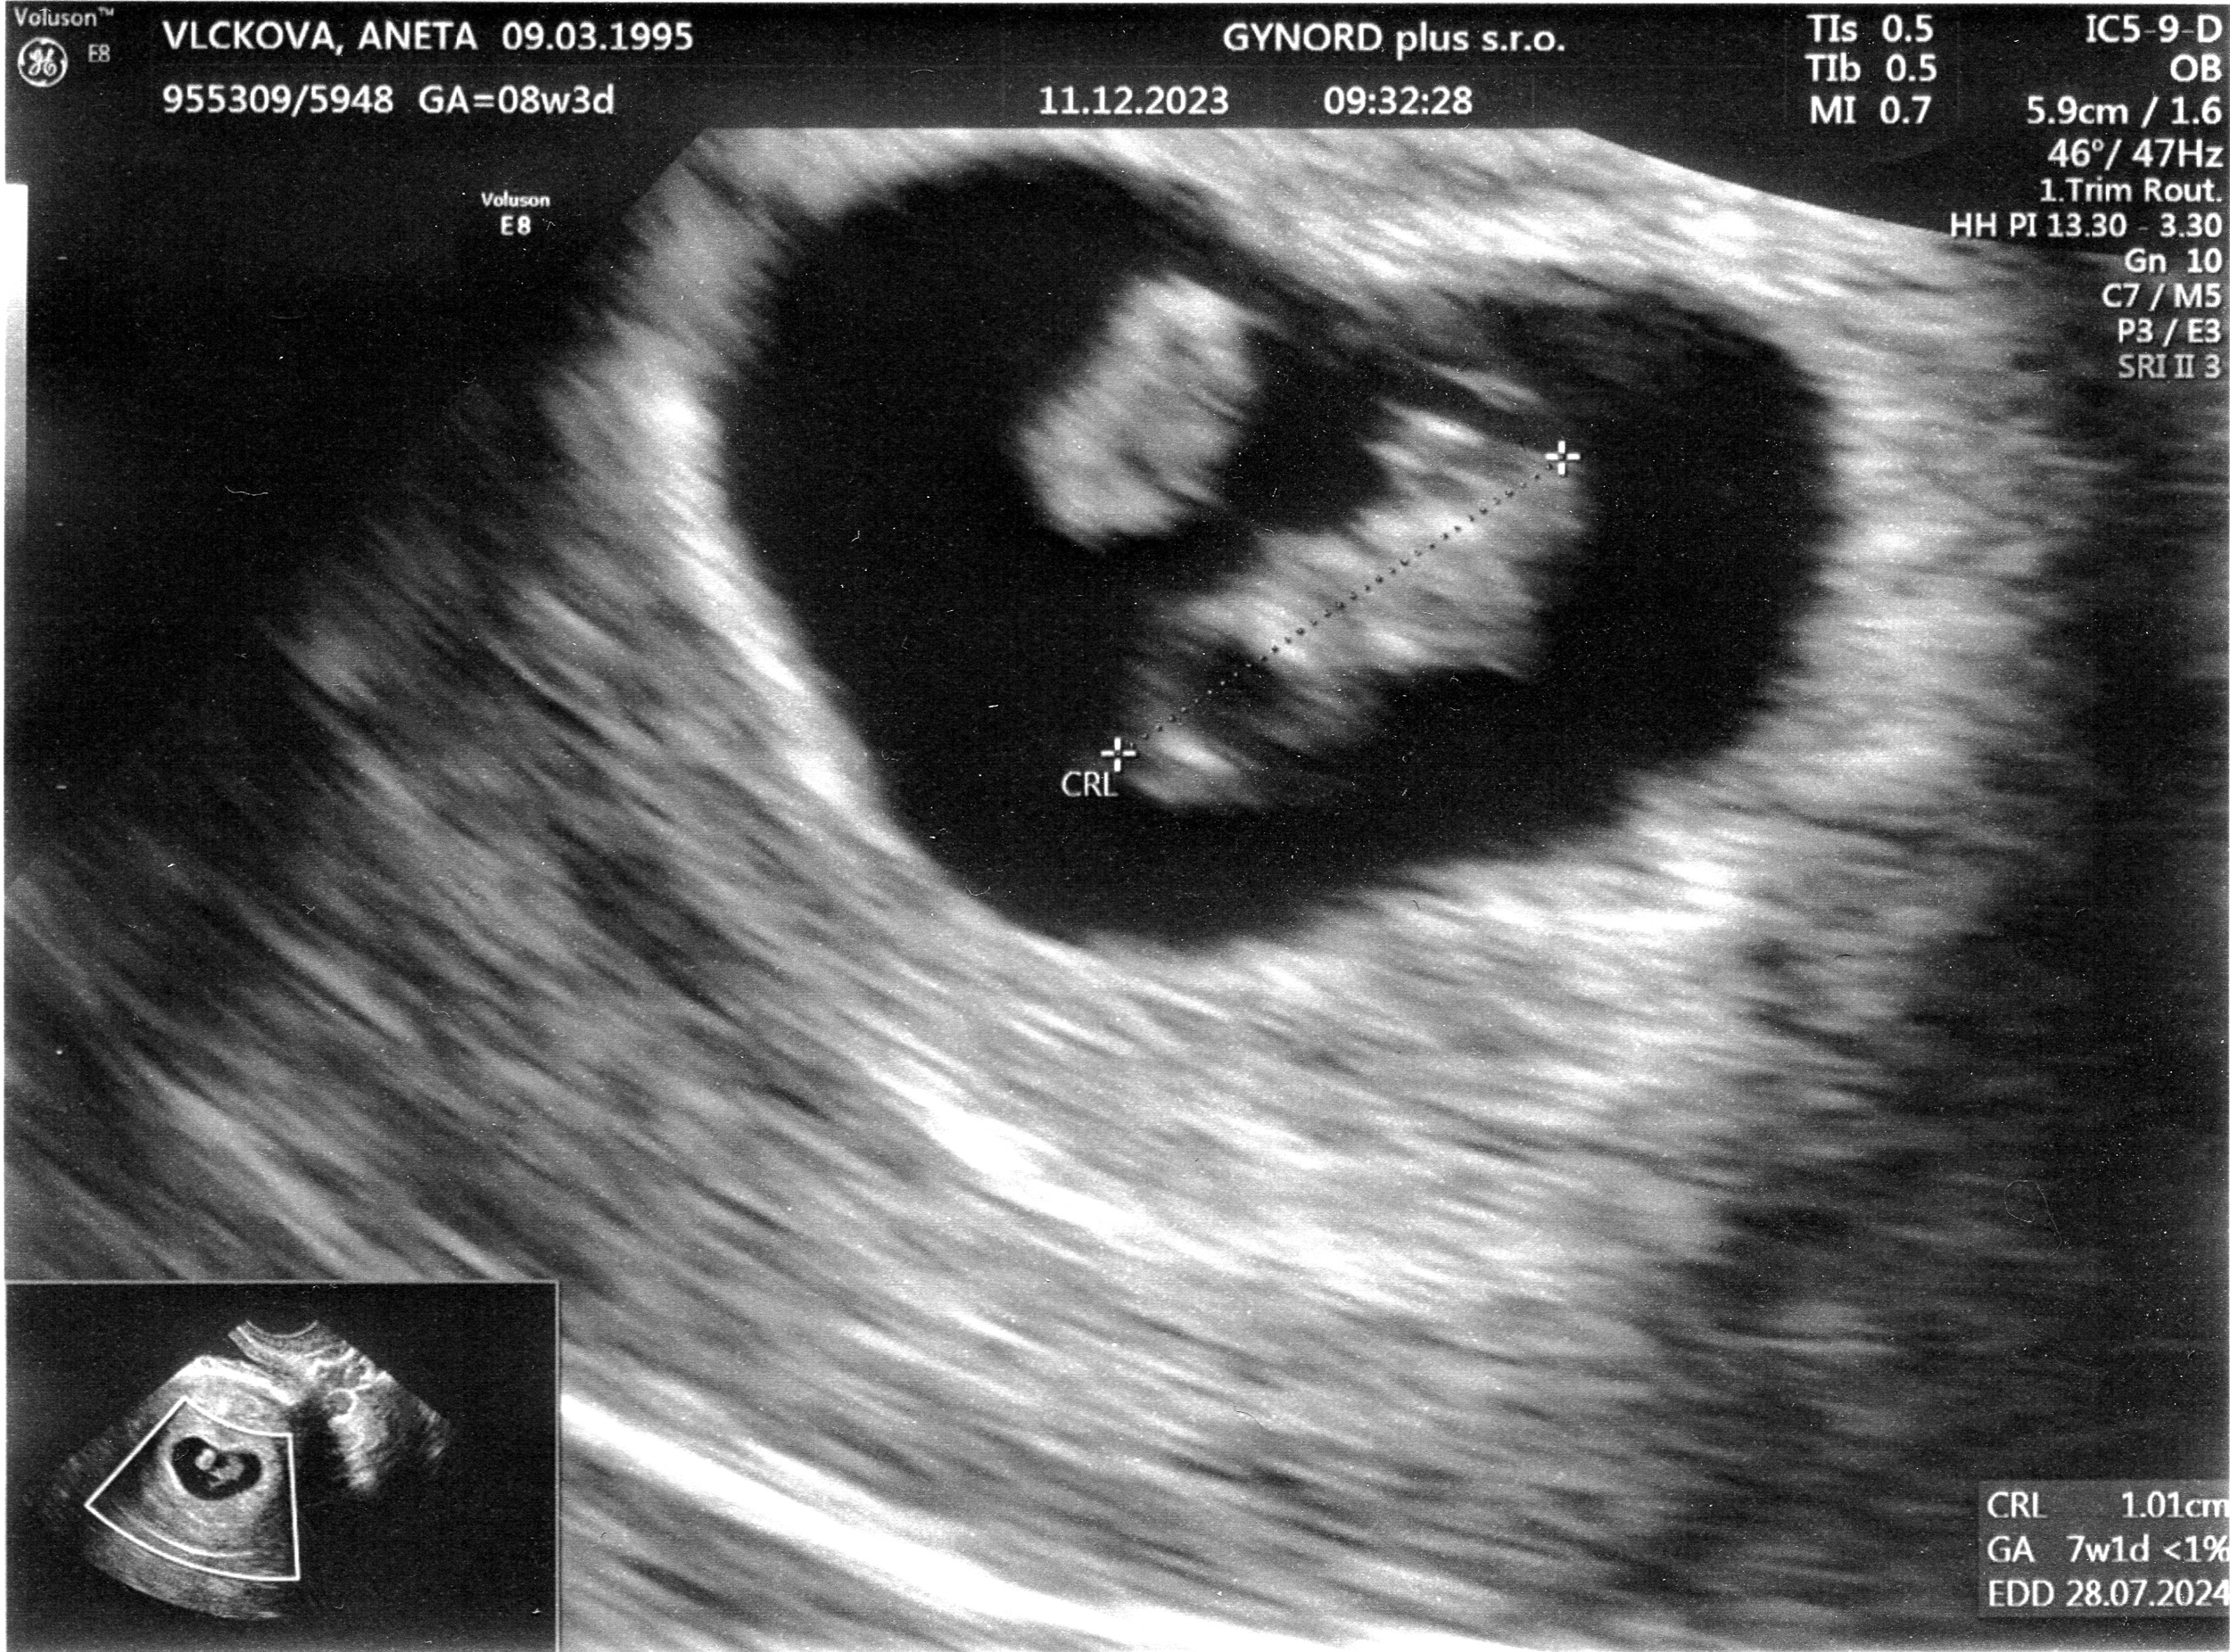

Tomášek - ještě v bříšku